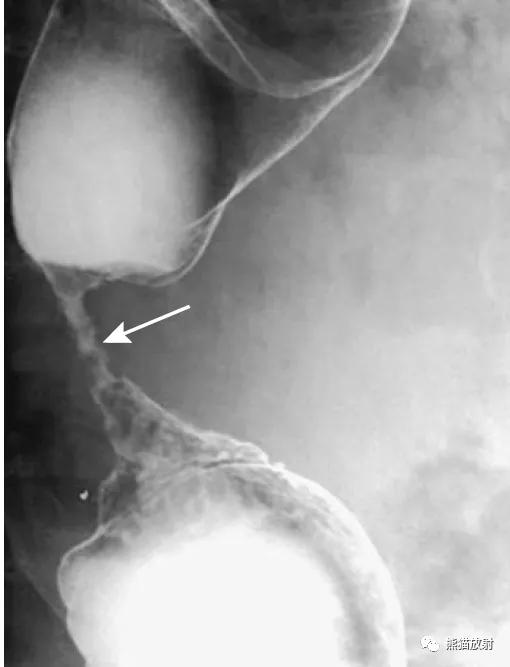

结-结肠肠套叠,由盲肠癌所致。钡灌肠显示横结肠中的肠套叠(箭头),在进一步的压力下,肠套叠移位至升结肠。